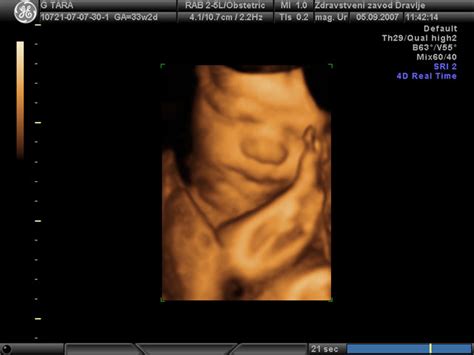

Če nosečnica preseže 40. teden, so pregledi pri ginekologu in babici pogostejši. S tem se skrbno spremlja stanje ploda, njegovi gibalni vzorci ter količina plodovnice. V primeru znakov majhnosti otroka ali drugih zapletov se lahko zdravniki odločijo za sprožitev poroda.